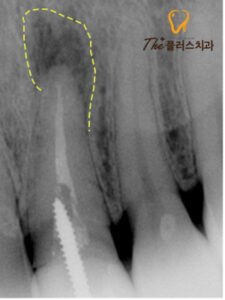

먼저 정확한 상태를 알아보기 위해

엑스레이 촬영을 진행하였는데,

판독해보니 신경치료를 진행한

치아의 뿌리 쪽에 염증이 재발생 한 모습을

볼 수 있었습니다.

하지만 예전 치료 시 신경치료 후

치아를 더욱 튼튼하게 사용하기 위해

포스트가 진행되어 있어

재신경치료가 불가능한 상태였습니다.